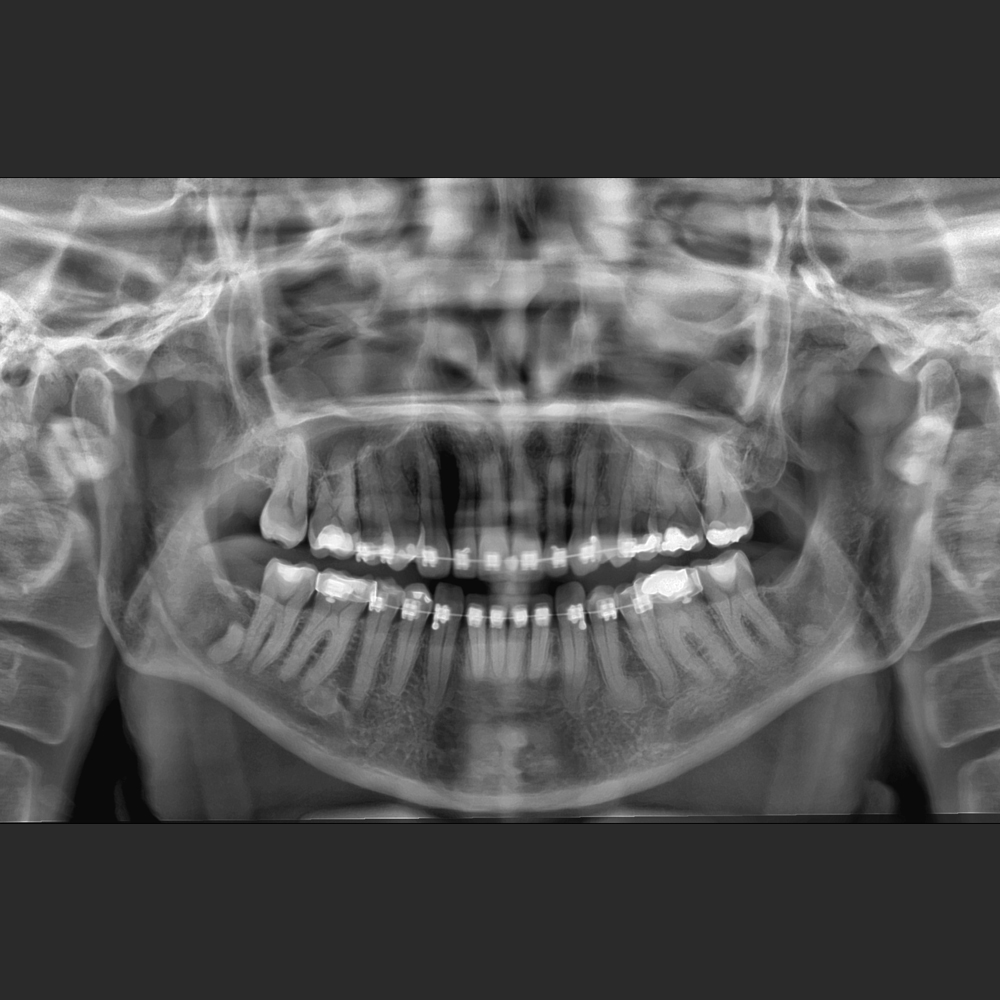

El Eagle 2D Pan/Ceph ofrece todos los exámenes en el perfil panorámico

(panorámica estándar, senos maxilares, baja dosis, bitewing, ATM, ortogonalidad perfeccionada, panorámica infantil y bitewing ortogonalidad perfeccionada)

Eagle Smart Contrast®

El algoritmo Eagle Smart Contrast® es una herramienta innovadora que actúa en todas las regiones de la imagen, tratando y perfeccionando el contraste de cada área individualmente. El resultado es uns imagen homopgénea y sin ruido, permitiendo la visualización de detalles y consecuentemente un mejor diagnóstico.